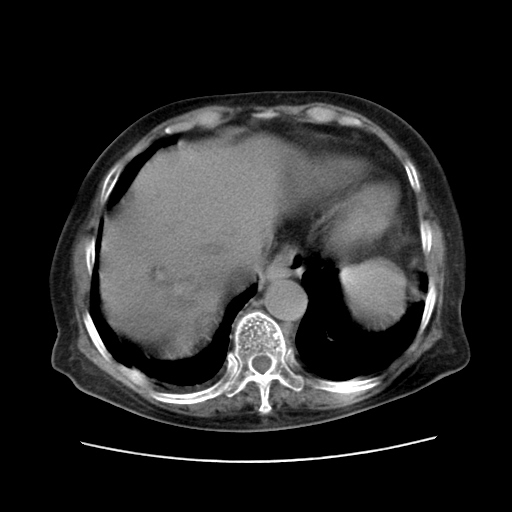

女,77.无不适

肝内胆管扩张,胆囊炎,胆囊窝积液。 右侧胸腔少量积液。

肝脏变异

肝右叶肝内胆管结石并肝内胆管扩张

胆总管扩张

右侧胸腔少量积液(也可能是胸膜增厚不过是什么都一样)

胆囊未见明显显影

肝右叶肝内胆管结石并肝内胆管扩张。另:慢性胆囊炎!胆囊窝积液!

肝右叶肝内胆管结石并肝内胆管扩张。胆总管下段梗阻,考虑壶腹部占位。

肝右叶肝内胆管结石并肝内胆管扩张。胆总管下段梗阻,考虑壶腹部占位。支持